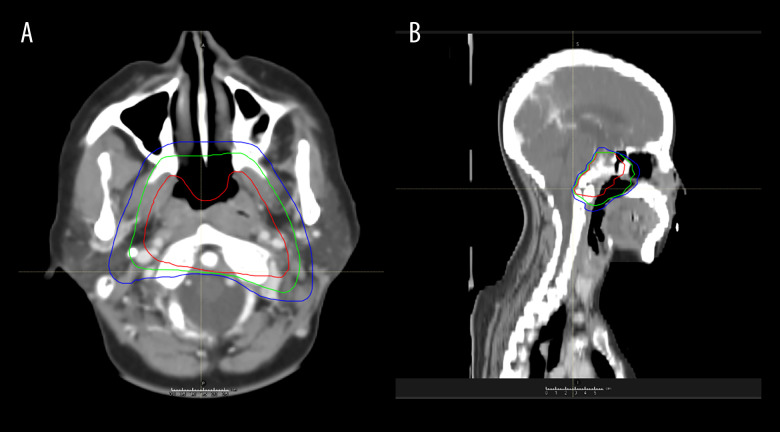

BACKGROUND Nasopharyngeal carcinoma can directly invade the intracranial cavity through skull base foramina in advanced-stage patients. Due to both the multiple cranial nerve injuries associated with nasopharyngeal base invasion and the proximity of the pituitary gland, it is challenging to differentiate this condition from intracranial space-occupying lesions, such as meningiomas and pituitary adenomas, in the early stages. This report describes a 37-year-old woman with bilateral nasal congestion, diplopia, hearing loss, and headache diagnosed with a large nasopharyngeal carcinoma invading the cerebellum, pons, medulla oblongata, and cervical spinal cord. CASE REPORT A 37-year-old woman with nasopharyngeal carcinoma (NPC) exhibiting extensive intracranial invasion - involving the mesencephalon, cerebellum, pons, medulla oblongata, and cervical spinal cord - was, with difficulty, diagnosed as having intracranial space-occupying lesions (meningiomas/pituitary tumors) by some renowned neurosurgical centers. She came to our hospital using a wheelchair, exhibiting vague pronunciation, decreased bilateral hearing, headache, facial numbness, diplopia, and coughing when drinking water. Following definitive diagnosis through nasopharyngeal biopsy confirming non-keratinizing carcinoma, we quickly proceeded with treatment. After receiving 6 cycles of chemotherapy with anti-PD-1 immunotherapy, followed by tomotherapy with concurrent nivolumab, the lesion was dynamically reduced, and efficacy was assessed as a complete response (CR). Therapy significantly improved her symptoms, with the holocranial headache resolving, intelligible speech restored, and facial sensation recovered. CONCLUSIONS This case highlights the importance of routinely integrating nasopharyngeal MRI and biopsy when evaluating patients with atypical cranial neuropathies. Furthermore, multidisciplinary team (MDT) collaboration is essential to avoid delayed diagnosis in NPC cases with extensive skull base invasion.